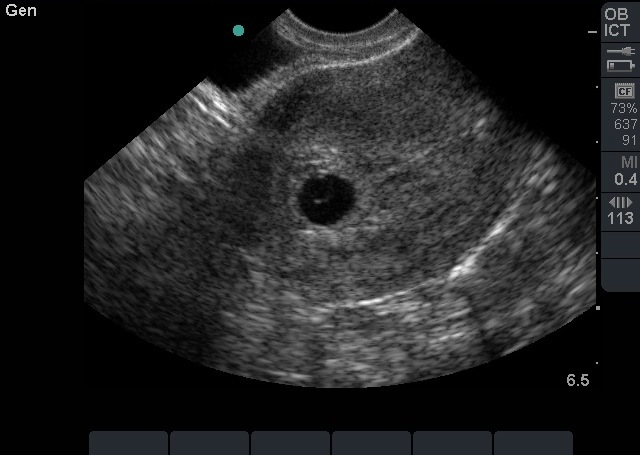

Bild 1 und 2: Transvaginaler (TV) Ultraschall des Beckens, Intrauteringravidität mit Dottersack, Zoom